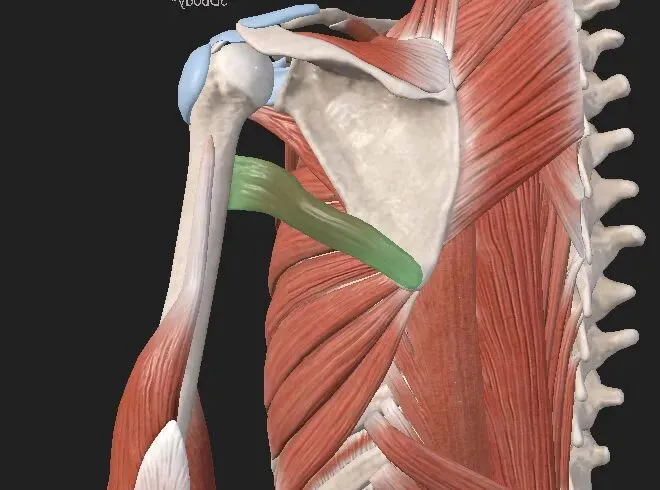

喙肱肌

起点: 肩胛骨缘突。

止点: 肱骨内侧缘的中部。

神经: 肌皮神经(C5、C6),起源于臂丛上、中干的前支。

喙肱肌: 顾名思义,从喙突连接到肱骨(臂)。这块肌肉是肱骨的弱屈肌和内收肌,如果这块肌肉变得张力很高,肩胛骨可能会向前倾斜,使肩膀呈圆弧形